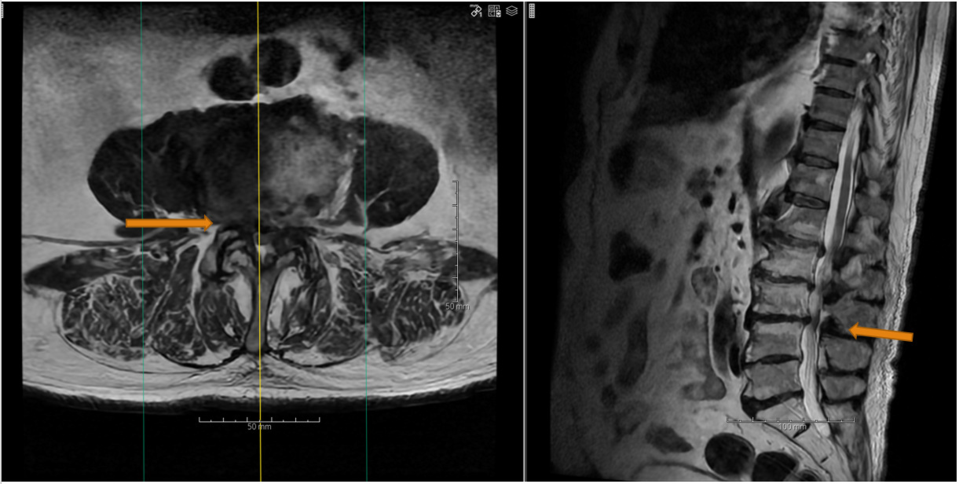

På det første billede ses, hvordan spinalnerven er klemt, inden den forlader rygsøjlen. På det andet billede ses, hvordan rygmarvskanalen forsnævres af fortykket væv ved slidgigt.